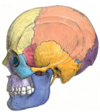

What are the bones of the cranial vault? (5)

1. Frontal

2. Parietal

3. Sphenoid

4. Temporal

5. Occipital

The _ separates the frontal and parietal lobes (2 Words)

Coronal suture